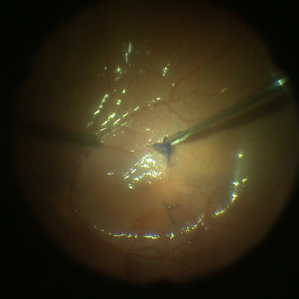

ILM Peeling in Progress

ILM Peeling in Progress

Feb 4 2022 by Manish Nagpal, MD, FRCS (UK), FASRS

Intraoperative shot of ILM peeling in progress using forceps.

Photographer: Manish Nagpal, Director, Retina Foundation, Ahmedabad

Imaging device: Sony PMW -10 MD surgical camera

Condition/keywords: ILM flap, ILM staining, internal limiting membrane (ILM) peeling, macular hole, retina, retina surgery